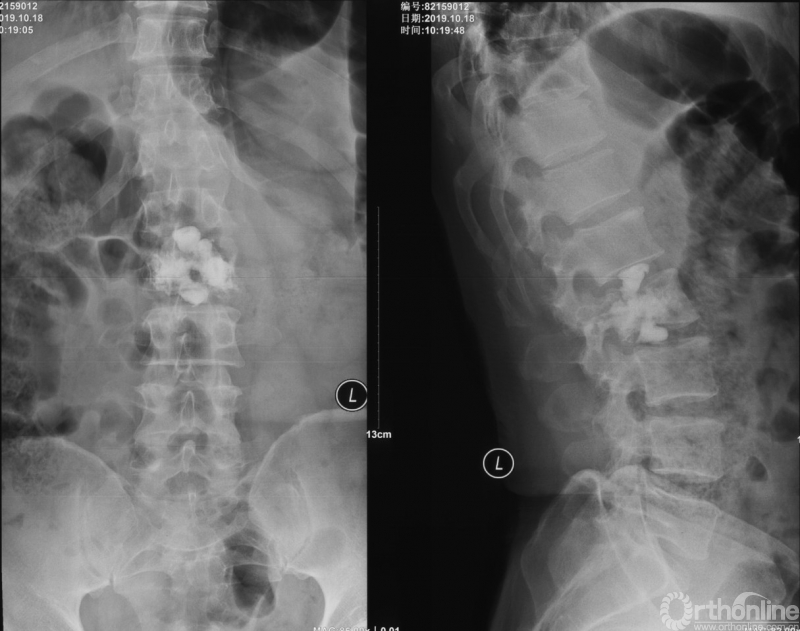

患者腰椎转移瘤术后9个月,因“腰痛伴右下肢疼痛麻木2个月”再次入院。既往在PVP术后曾行化疗及服用埃克替尼靶向药物维持治疗,查体一般状况良好,自主行走,右大腿前外侧麻木。

入院影像学资料

经脊柱转移瘤专业评估,ESCC分级为Grade2,对放疗不敏感;SINS评分8分,中度不稳。Karnofsky功能状态评分90%,预计生存时间6个月。NOMS流程建议分离手术和SRS。

常规分离手术可进行360°脊髓减压,充分固定恢复脊柱稳定;但由于其暴露范围广泛,创伤较大,并不适宜患者当前治疗。

为进一步减少创伤,获得更好的综合疗效。骨采用经皮内固定的微创杂交技术,暨经皮内固定结合小切口分离手术,手术失血900ml,术后7天出院。